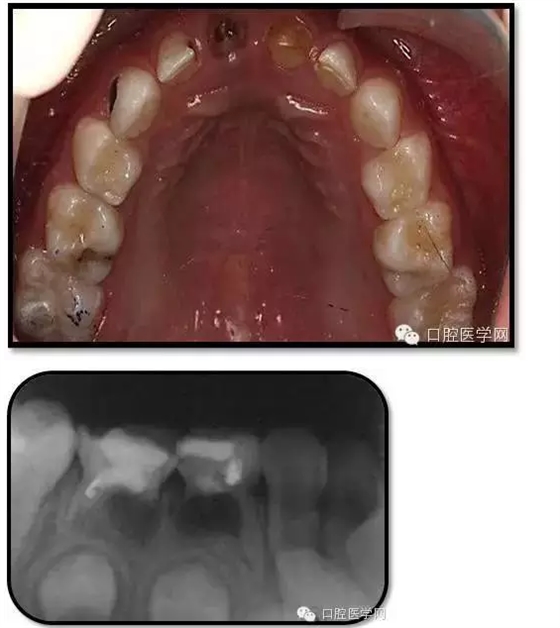

臨床檢查: 75OL齲洞, 舌側(cè)牙體完全劈裂斷端齊齦,探及大量軟化腐質(zhì)。頰側(cè)牙齦紅腫見瘺管,擠壓大量溢膿。叩(±),不松動(dòng)。X線:75根管空虛,牙根吸收約1/2,根尖周及根分歧大面積透射影,35發(fā)育4期,骨硬板尚連續(xù);51殘根,唇側(cè)牙齦瘺管,叩(±),不松動(dòng)。X線:51牙根吸收約1/2,根尖周低密度影。

85O、84DO充填體邊緣不密合,叩(±),不松動(dòng)。84頰側(cè)牙齦略紅腫。X線:84遠(yuǎn)中根及髓室底完全吸收,根分歧透射影,近中根內(nèi)側(cè)見外吸收,44上方骨硬板連續(xù)。85近中根完全吸收,髓室底吸收,根分岐透射影,遠(yuǎn)中根管內(nèi)見根充影像。45發(fā)育4期,骨硬板連續(xù)。

85O、84DO充填完好,邊緣密合,叩(-),不松,齦無紅腫。X線:84、85根分歧透射影,44、45骨硬板連續(xù),恒牙胚上方骨板厚約2-3mm。75帶環(huán)絲圈式間隙保持器完好,無松動(dòng),無咬合不適。64MO中齲。 64MO中齲去腐凈,自酸蝕,SEBOND,樹脂充填。 口腔衛(wèi)生宣教,囑3個(gè)月后復(fù)診。

1、根分歧處病變姑息保留牙的治療及轉(zhuǎn)歸。 75牙體缺損過大,根分岐大面積透射影并累及根尖周。故拔除后間隙保持。84、85初診時(shí)已做過根管治療,有繼發(fā)齲,牙根吸收較多,可見大面積的根分歧病變,但根尖無病變,考慮44、45表面骨硬板連續(xù),故只對(duì)患牙進(jìn)行了繼發(fā)齲充填治療,姑息保留。3個(gè)月復(fù)查時(shí),85O、84DO充填完好,邊緣密合,叩(-),不松,齦無紅腫。7個(gè)月復(fù)查時(shí)85O、84DO充填完好,邊緣密合,叩(-),不松,齦無紅腫。X線:84、85根分歧透射影,44、45骨硬板連續(xù)。 回顧整個(gè)治療過程,應(yīng)定期復(fù)查84、85姑息保留牙,且間隔時(shí)間不宜過長(zhǎng)。觀察根分歧病變的恢復(fù)情況,一旦發(fā)現(xiàn)恒牙胚受累及,則需采取積極措施。